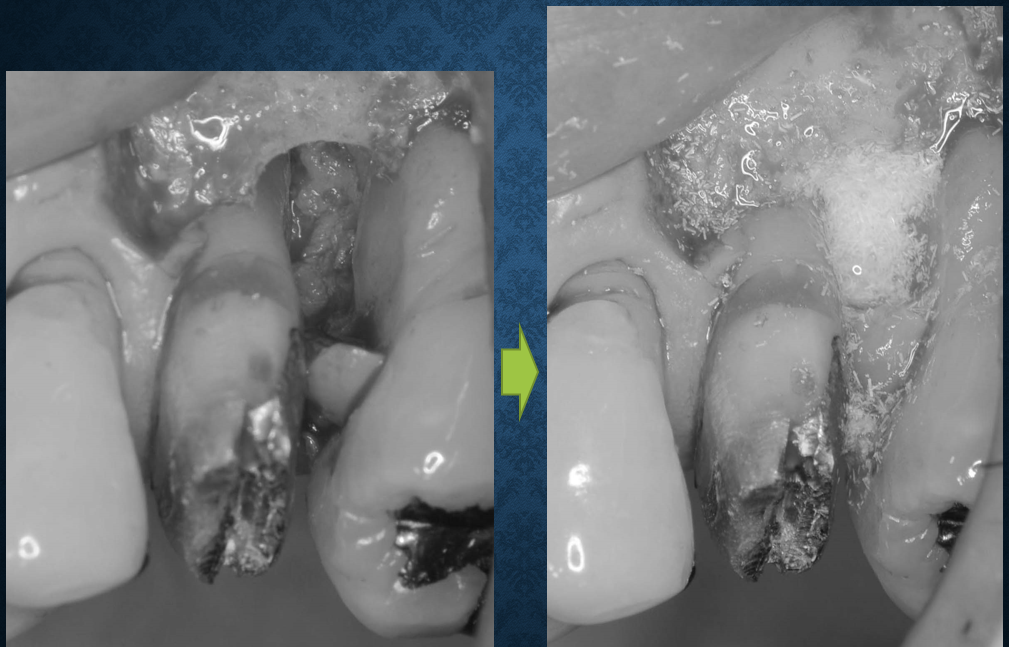

約1年前に歯周組織再生療法を行った患者さんがメンテナンスで来院されました。歯周組織のある程度の回復が確認され、歯周ポケットも浅くなり改善が認められました(写真をクリックして拡大してご覧ください)。比較的やりやすい単根歯であったことと患者さんのメンテナンス協力度がカギだったと思います。来月には福岡で水上哲也先生の歯周治療の考え方の変革と銘打って実習付きのセミナーに参加予定です。手技上の改良を加えて、より効率的なオペを目指したいと思います。